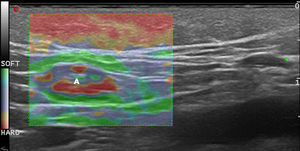

Malignant Skin TumorsElastography shows that malignant skin tumors are stiffer than the surrounding tissue18 (Fig. 5).

Dasgeb et al.25 studied 55 patients with a total of 67 epithelial tumors, of which 29 were malignant (17 basal cell carcinomas and 12 squamous cell carcinomas) and 19 were benign. In this study, the strain ratio was > 3.9 in all malignant skin tumors and < 3 in all benign skin tumors. For strain ratio values between 3.00 and 3.9, sensitivity and specificity were 100% in the diagnosis of malignant lesions.

Elastography has been used to study melanoma. In a pilot study by Botar et al.,26 42 melanomas in 39 patients were studied using SE and color Doppler ultrasound to assess vascularization.

The melanomas were hypervascularized and had multiple vascular pedicles, and SE showed that the lesions were stiffer than the adjacent skin. The lesions with the highest degree of vascularization had the greatest stiffness.

The correlation between melanoma neovascularization and prognosis is well known in the literature.27,28 Therefore, lesion stiffness could be a prognostic factor in melanoma.29